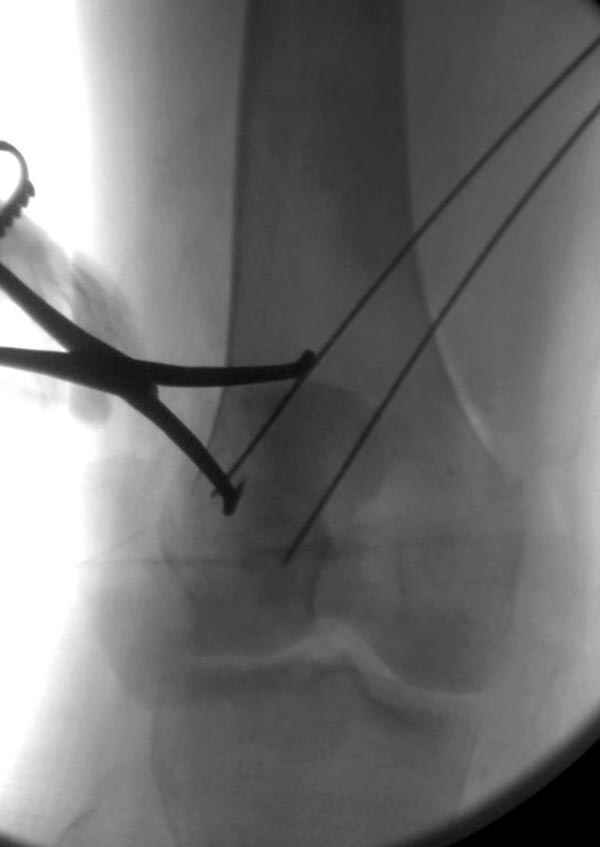

Сегодня досылаю остальные снимки, которые не прошли вчера. Как вчера писал, после фиксации перелома надколенника с дефектом кости и собственной связки, наложили ваккуум и наружный фиксатор. (снимки 4-9)

Внешний фиксатор держим около 6 недель, поэтому был выбран метод фиксации шурупами и еще линия перелома была диагональной, не было нужды в tension band technique, cannulated screws удобнее, провел спицы и по ним шурупы.

Связка ушита обычными сухожильными швами конец в конец, не было нужды проведения шва через надколенник, из-за ех-фиксатора.